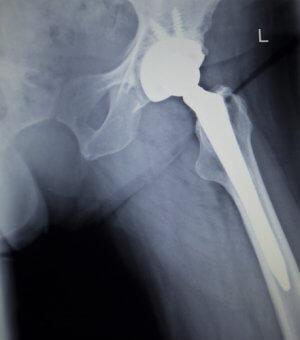

Предварительный период: индивидуальный подбор протеза. Благодаря 3D-визуализации врач подбирает такую модель протеза, которая максимально анатомически совпадает со строением «родного» сустава пациента. Протез представляет из себя многокомпонентную конструкцию, состоящую из ножки, головки и искусственной суставной впадины (ложа). Ножка обычно выполняется из титанового сплава с покрытием специальным пористым материалом (для лучшей фиксации к кости). Для того, чтобы головка свободно скользила в суставной впадине, она тщательно отполирована. Ложе обычно выполняют из полимерного материала. Собранные воедино, все части протеза обеспечивают естественную подвижность сустава. Материалы, из которых делают протезы, не подвержены коррозии и полностью совместимы с человеческими тканями. В данный момент в клинике СТС используют наиболее современные вида протезов из титана, керамики и полимеров, срок службы которых максимально возможный на сегодняшний день – до 30 лет. При выборе модели учитывается возраст больного и степень его двигательной активности. Так, для молодых людей выбираются те, которые меньше всего снашиваются, даже если пациент будет активно двигаться.

Операция. Операция проходит под наркозом, общим или эпидуральным. Во время хирургического вмешательства осуществляется контроль за ее ходом при помощи новейших навигационных систем, что позволяет хирургу действовать максимально точно. Пациента укладывают на бок, хирург делает разрез для доступа к оперируемой зоне. В данный момент хирурги клиник СТС выполняют доступ максимально бережно, например, по возможности, мышцы и связки не разрезаются, а раздвигаются. Затем происходит извлечение разрушенной хрящевой и костной ткани, после чего осуществляется непосредственно установка протеза.

Сначала в костный канал устанавливают ножку с головкой, к ней присоединяют искусственное ложе.

Хирурги клиники использую разные подходы для крепления импланта. Может быть использован специальный костный цемент (клей), который скрепляет кости и эндопротез. Возможен и другой метод: элементы крепления импланта впрессовываются в костную ткань, через какое-то время происходит сращивание поверхности «родной» кости и импланта, за счет пористой поверхности ножки протеза. В некоторых случаях возможна комбинация этих двух методик: часть сустава прикрепляется путем естественного сращивания, часть – скрепляется медицинским цементом.